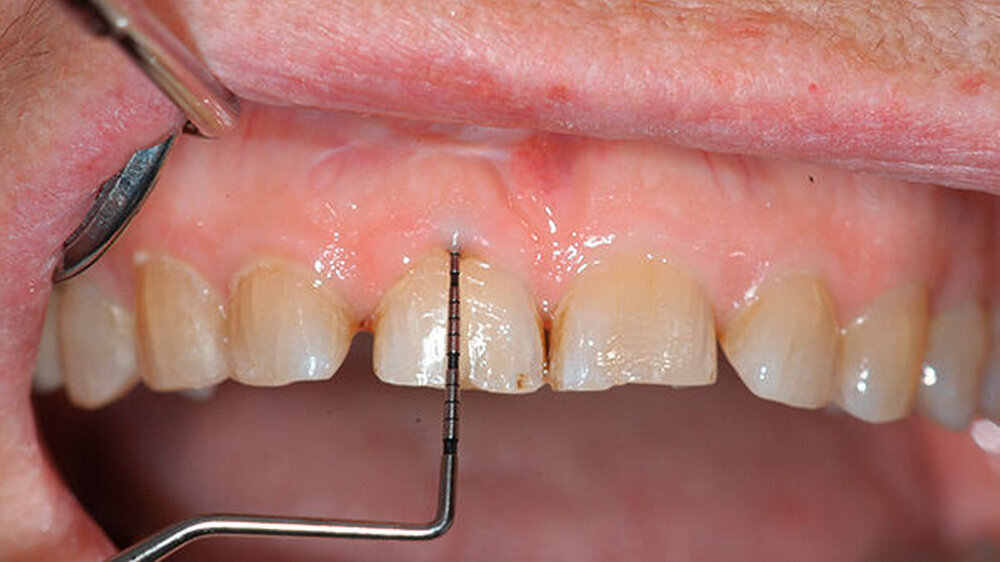

Bei der Vorstellung in der Poliklinik zeigte sich klinisch eine Schmelzfraktur auf der bukkalen Fläche des Zahns 11 (Abbildung 1). Die Messung der Taschensondierungstiefe (TST) ergab an dieser Stelle lokal begrenzt einen Wert von 7 mm (Abbildung 2). An allen übrigen Messpunkten lag eine physiologische TST von 3 mm vor.